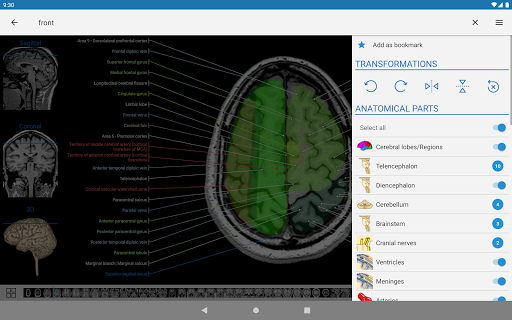

e-Anatomy tiene más de 26 000 imágenes que contienen series de imágenes en vistas axiales, coronales y sagitales, así como radiografías, angiografías, imágenes de disección, gráficos anatómicos e ilustraciones. Todas las imágenes médicas fueron etiquetadas cuidadosamente, más de 967 000 etiquetas disponibles en 12 idiomas, incluida la Terminologia Anatomica latina.

- Desplácese por los conjuntos de imágenes arrastrando el dedo

- Acerque y aleje el zoom

- Toque las etiquetas para mostrar las estructuras anatómicas

- Seleccione las etiquetas anatómicas por categoría

- Localice fácilmente las estructuras anatómicas gracias a la búsqueda de índice